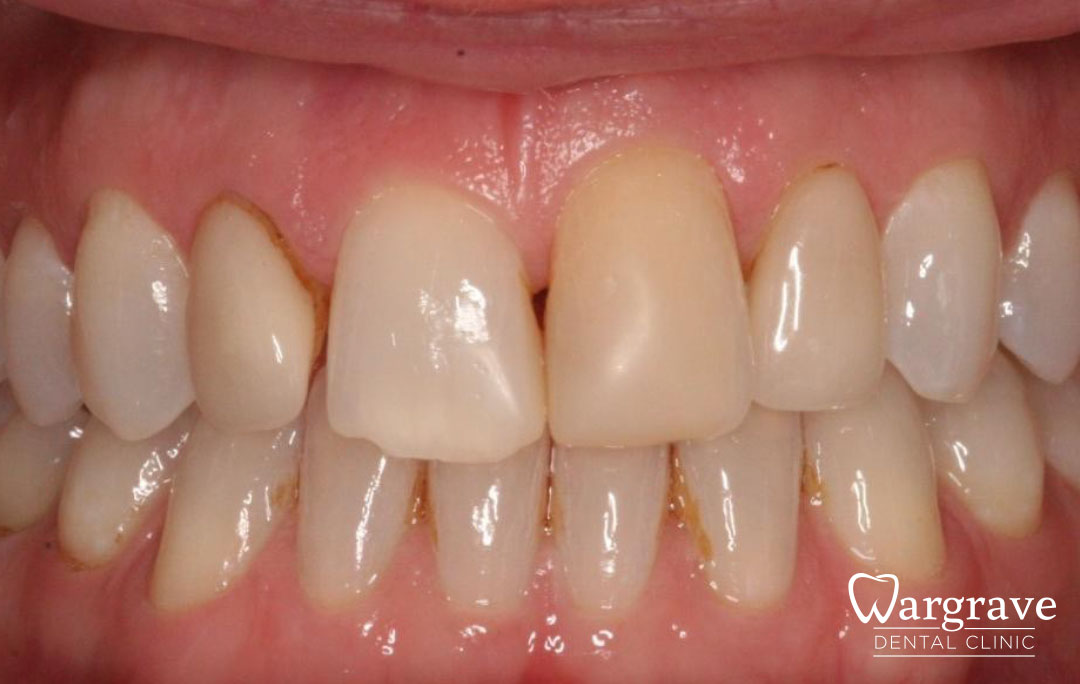

Healthy Smiles These are more advanced examples of different treatments available.All cases shown were carried out by Dr R Khurana unless otherwise stated. Immediate implants Anterior Mandible Bone Regeneration Anterior Mandibular Implant Bridge Maxillary Anterior Implant Bridge Implant stabilised ‘Life Like’ replacement dentures Implant Bridge after 10-years with zero bone loss Implant examples including ZBLC concepts Adhesive Bridge solution for a missing premolar Multidisciplinary care Orthodontics, Replacement veneers and composite bonding Adhesive Bridge solution for missing central incisors Replacement crown, Veneer and Composite Bonding Replacement Crowns and Veneer Injection Moulding using Composite Resin Equilibration Tooth Whitening to treat Developmental Discolouration